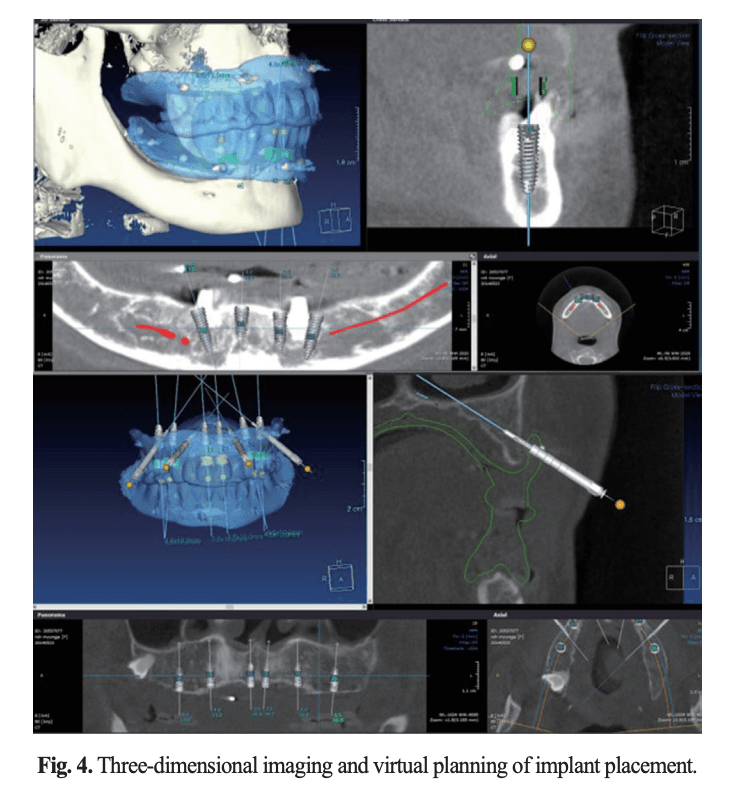

3차원 영상과 소프트웨어 상의 임플란트 가상 식립 계획

[그림 2] CBCT로 얻은 3차원 해부학 정보를 소프트웨어에서 재구성하고, 보철 위치에 맞춰 임플란트의 길이·각도·식립 위치를 가상으로 설계합니다.

디지털 가이드 수술의 핵심은 “수술 전에 수술을 끝내 두는 것”입니다. CBCT로 촬영한 환자의 3차원 해부학 정보와, 임시 총의치에 내장한 방사선 마커를 중첩(스캔 데이터 중첩, superimposition)시켜 보철물 위치와 임플란트 축을 소프트웨어 상에서 최종 확정한 뒤, 그 계획대로 3D 프린팅 수술용 스텐트를 제작합니다.

• 2단계 — 그 보철물 위치에서 거꾸로 임플란트 축을 결정합니다. CBCT 데이터와 소프트웨어(NeoGuide 등) 상에서 보철물-임플란트-골의 3차원 관계를 분석합니다.

계획된 식립각과 위치를 구강 내에서 재현할 수 있어, 후방 경사 식립·보철 축 정렬이 정밀하게 이루어집니다.

③ 예지성 (Predictability)

최종 보철물을 미리 디자인한 상태에서 식립하기 때문에, 수복 후 결과가 어긋날 가능성이 낮습니다. 즉시 부하(immediate loading) 계획도 안전하게 수립할 수 있습니다.